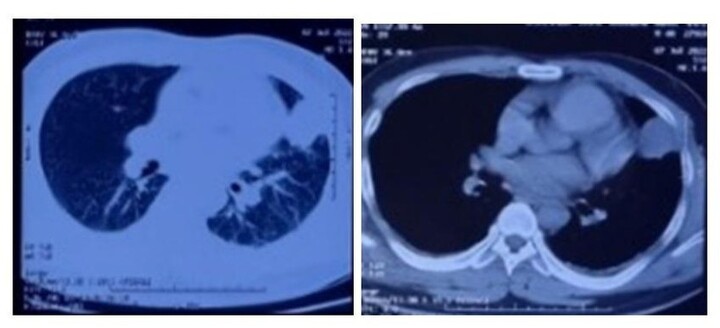

Theo đó, bệnh nhân nam sinh năm 2007 ngụ tại thị xã Nghi Sơn (Thanh Hóa) nhập viện trong tình trạng rất nặng: phổi tổn thương, suy hô hấp, có ban sẩn xuất huyết ở 2 bàn tay, thở máy, duy trì vận mạch. Bác sĩ chẩn đoán trẻ bị sốc nhiễm khuẩn, suy đa tạng, mắc bệnh Whitmore.

Vi khuẩn theo dòng máu đến khắp các cơ quan, nhất là gan, lách, phổi, dẫn đến các ổ áp xe từ nhỏ đến lớn hoặc có thể liên kết với nhau. Nếu không phát hiện sớm và điều trị kịp thời, bệnh diễn tiến trầm trọng, sốc nhiễm khuẩn, suy đa tạng, có thể tử vong.